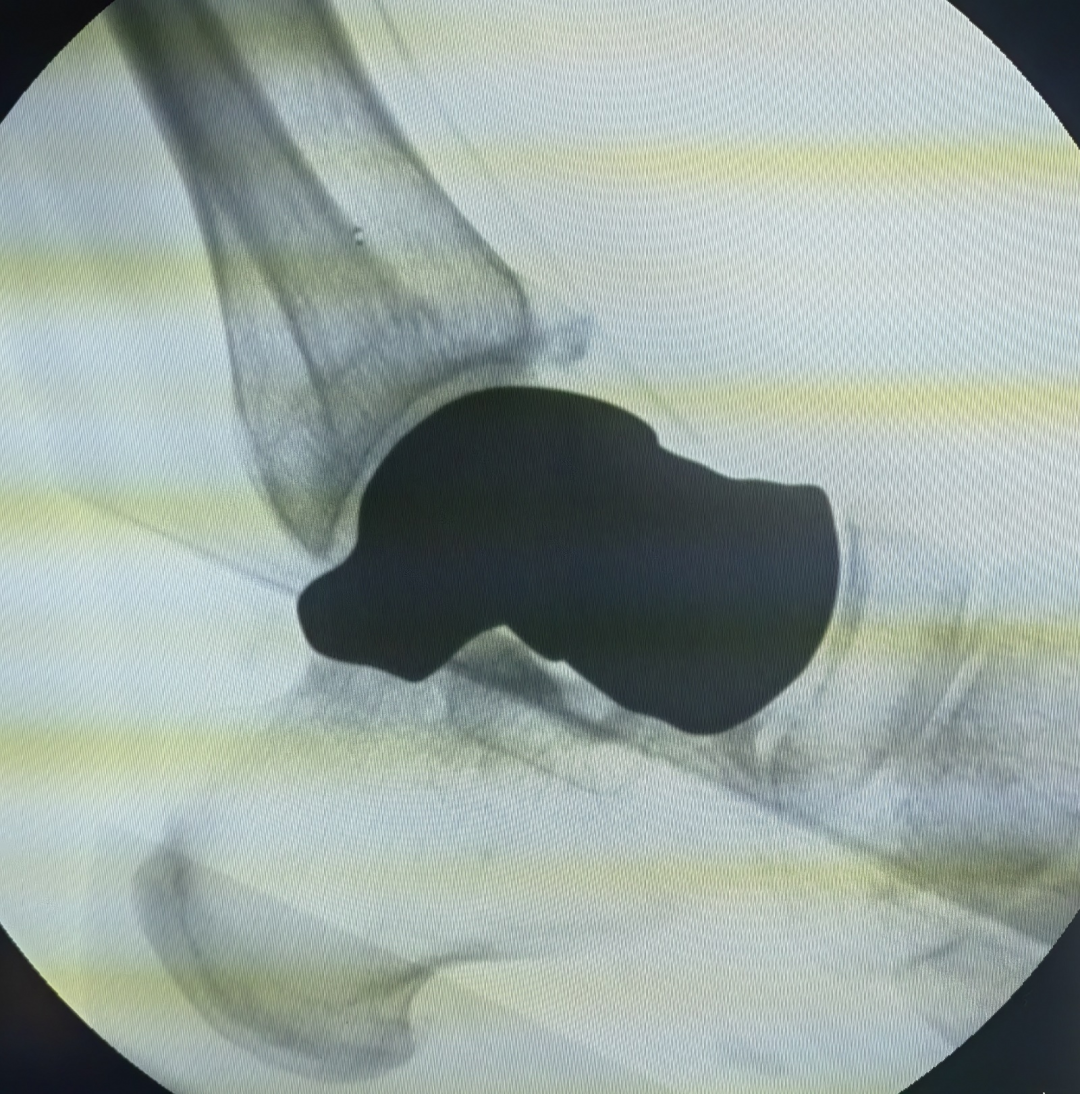

手术团队根据影像学资料为患者量身定制,打印人工距骨假体植入。为了保证手术成功开展,术前多次进行生物力学试验和模拟手术。打印的距骨假体材料为钛合金,具有组织相容性好、耐磨、寿命长的特性。经过1小时的紧张手术,3D打印距骨假体被成功植入患者体内,放至位置精准,与周围组织结构契合牢固,手术成功完成。

距骨假体植入位置精准